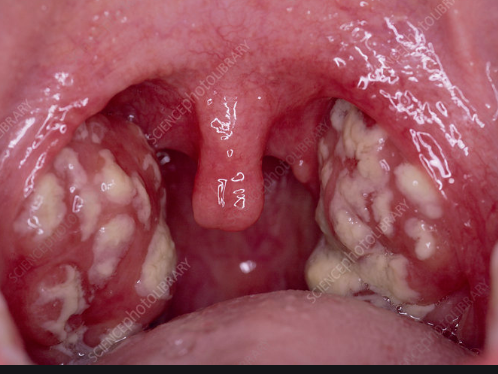

Bademcikler boğazın arka kısmında her iki yandaki kıvrımlar içine yerleşmiş oval şekilli organlardır. Bademcik enfeksiyonu anlamına gelen latince kökenli “tonsillit” ifadesi hem tıp dilinde hem günlük konuşmada yaygın olarak kullanılmaktadır.

_Kızarık ve şişmiş bademcikler

_Bademcikler üzerinde sarı-beyaz plaklar